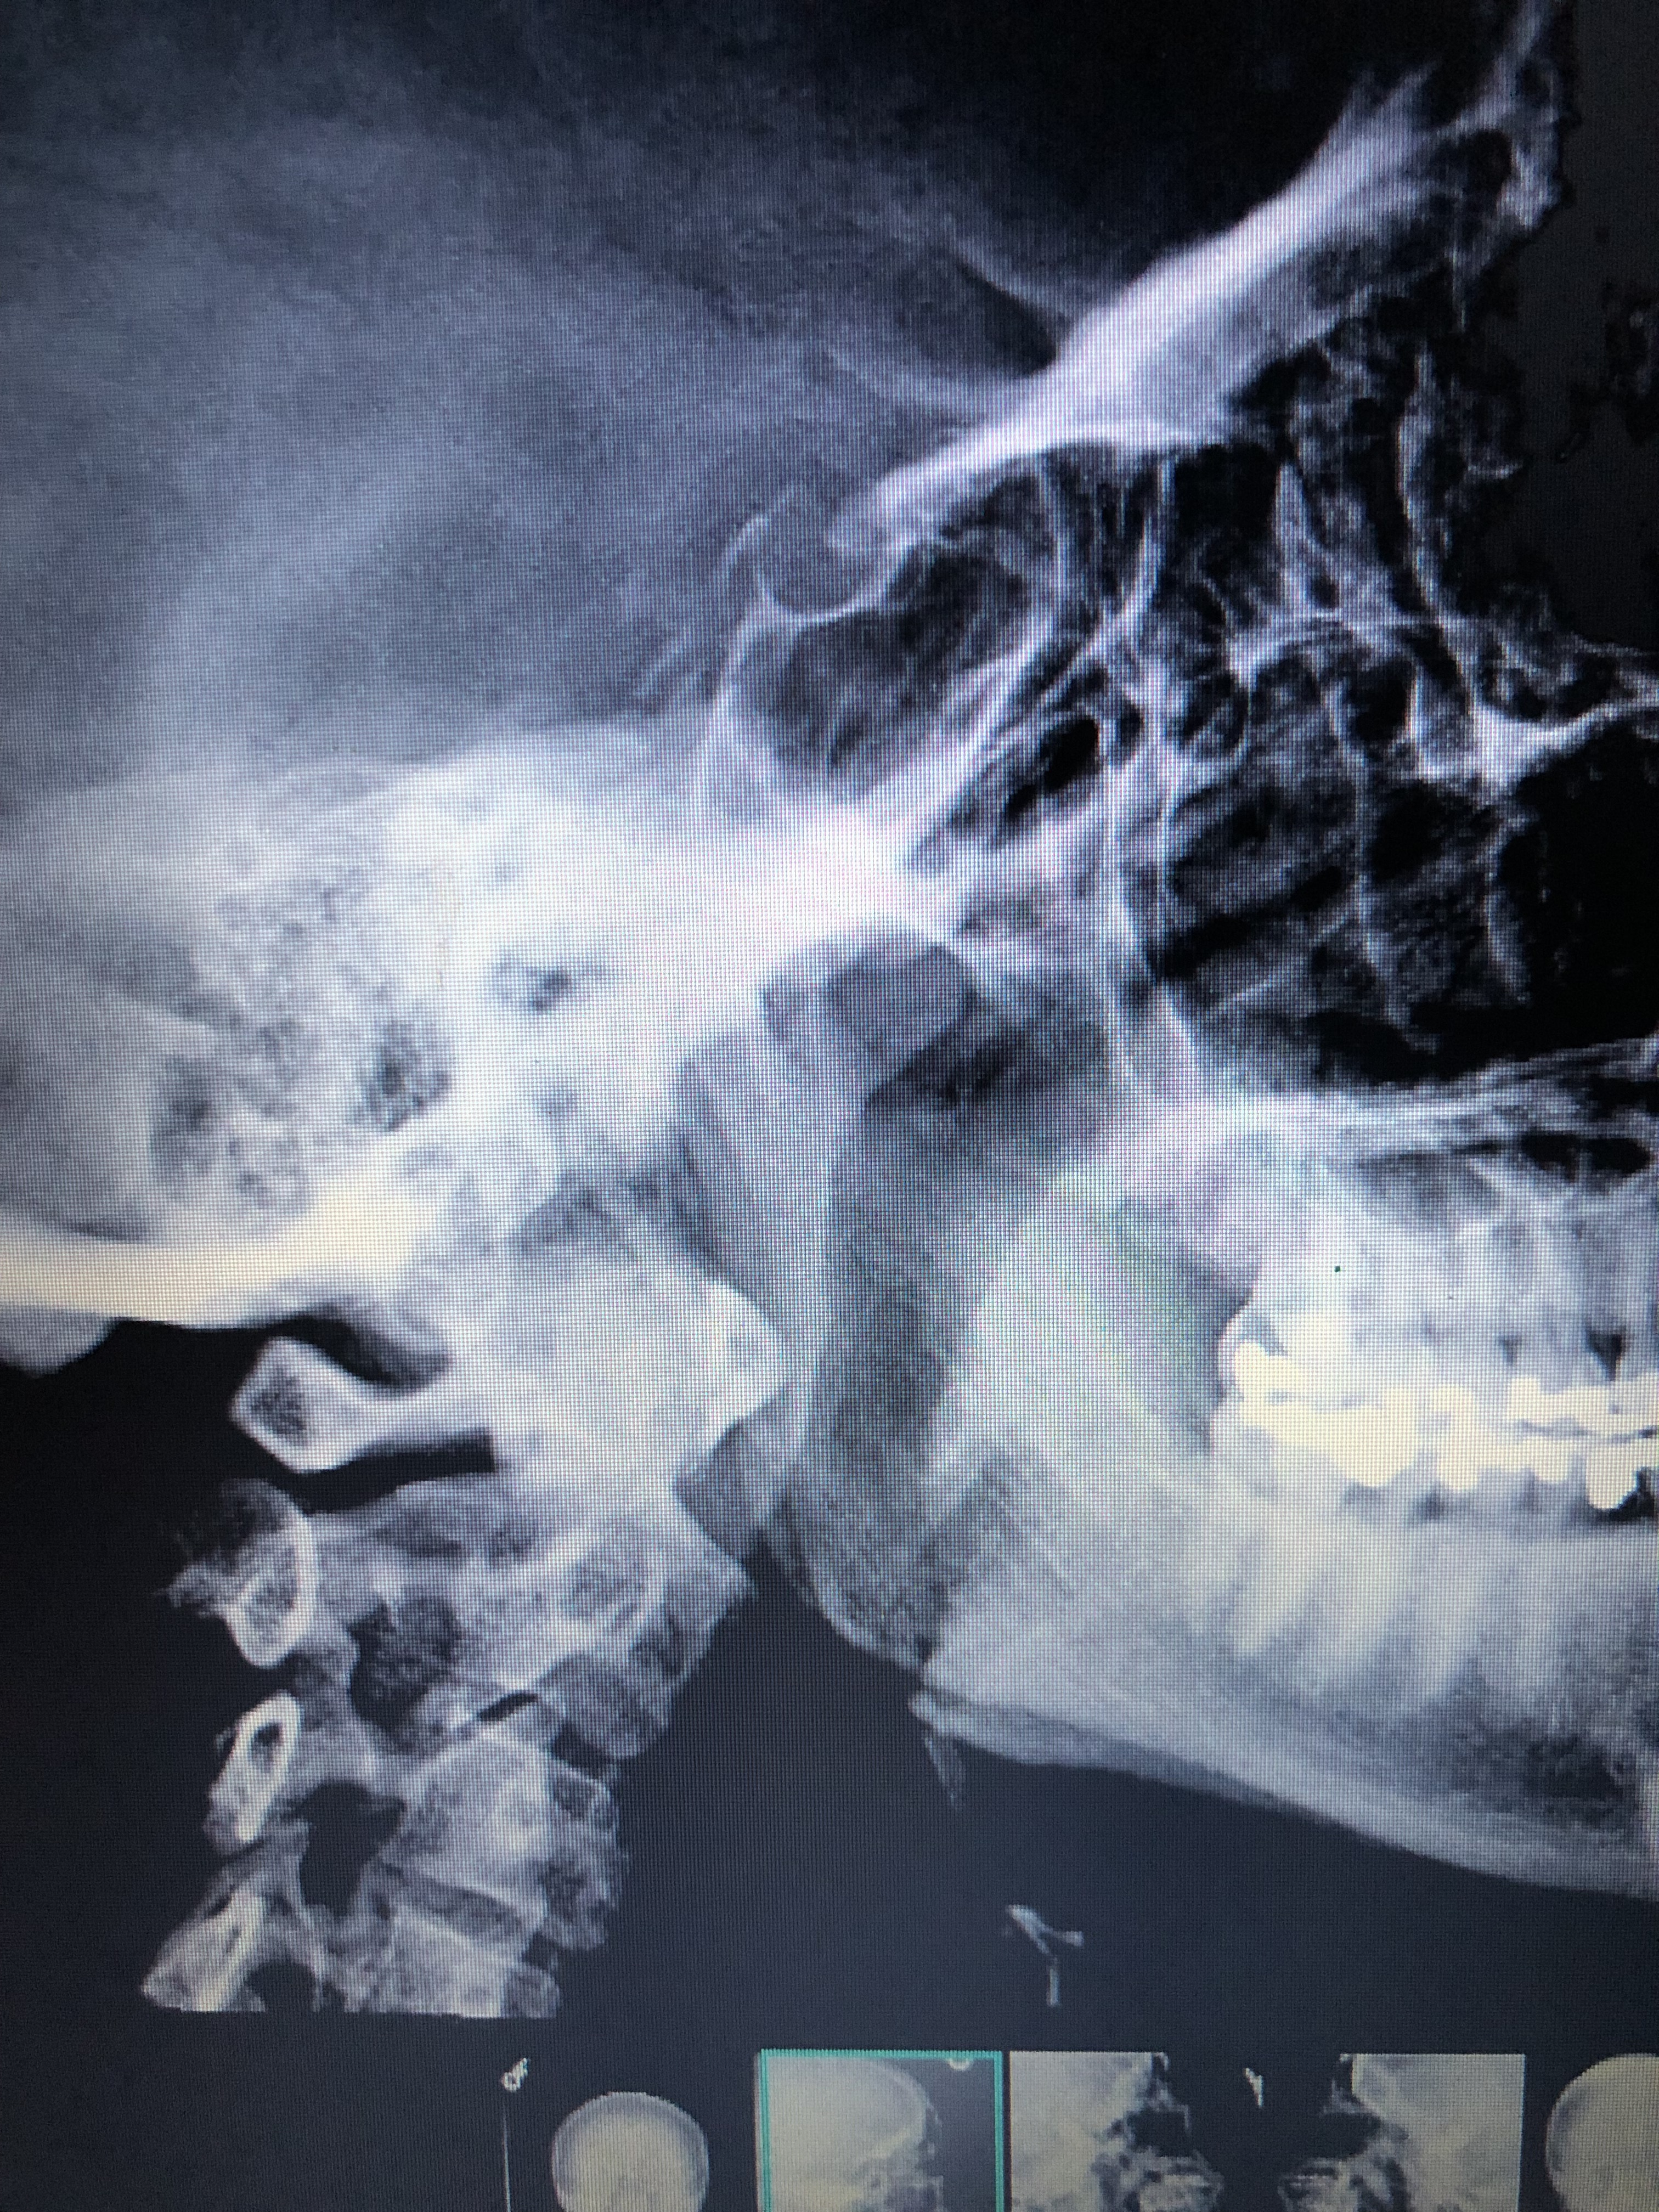

My potential diagnosis came when my dentist discovered the ligaments in my jaw are calcified. He dismissed it, but I began doing some research on my own and that’s when I found out about Eagle Syndrome. I brought this information to my doctor at the VA and she ordered a set of x-rays. The report came back with probable stylohyoid ligament ossification and now I’m waiting to be scheduled for a CT and a referral to ENT.

I have included a picture of one of my x-rays just to see if anyone notices anything regarding my ligaments or the styloid process itself. Thank you for any advice or help you can provide.

The styloid looks quite long & pointy, there’s a possible little bit of calcification further down too. But obviously we’re not doctors!

Thank you! That’s what I thought as well, but it is good to know that someone else sees it too.